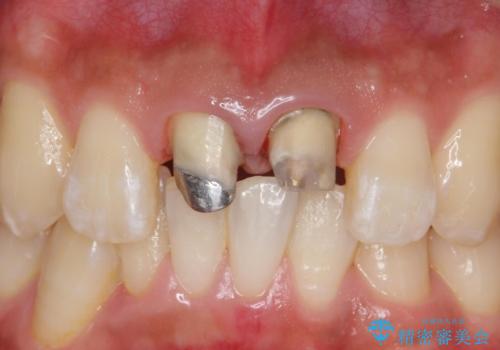

- 前歯のかぶせ物の変色を主訴に来院された患者様です。

根管治療からのやり直しはご希望されませんでした。

今回はe-maxクラウンで修復していきます。